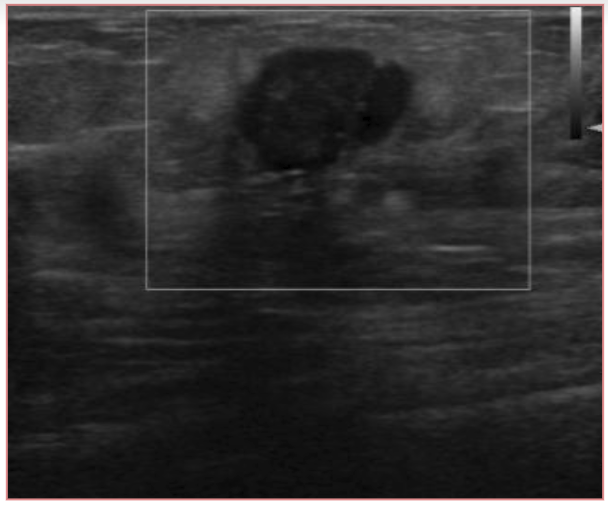

Ultrasound is well accepted as the most useful adjunct to mammography for the diagnosis of breast abnormalities. An exemplary ultrasound image of right breast of a patient is shown in Fig. 4. Ultrasound is most often used to assess palpable masses and nonpalpable masses that have been detected during screening mammography [20, 21]. Ultrasound may demonstrate malignancies and other masses that are not visible mammographically [22]. Ultrasound had an overall pooled sensitivity and specificity of 80.1% and 88.4%, respectively [11].